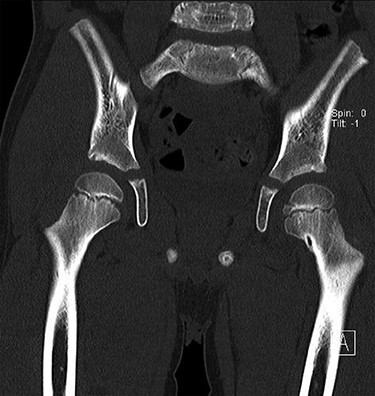

CT hips reported a well-defined lesion seen bilaterally in the neck of femur anterior infero-medial aspect, more prominent on the left side measuring 7 x 3 mm on left side both in coronal (Fig. 3) and axial (Fig. 4) views. On the right side, other lesion measuring 2 x 1 mm (Fig. 5) seen in coronal view. These two lesions are well defined with a sclerotic border with a small cortical defect. The lesion shows fat density. The symmetrical appearance of the lesion combined with the fat density and location suggest the diagnosis of synovial herniation pit. MRI Pelvis revealed minimal left hip joint effusion with loculated fluid seen along the trochanteric bursa with the largest measuring 0.9 x 1.5 cm (Fig. 6, 7).

Showed coronal cut of CT hips demonstrating the synovial pit prominent right side.